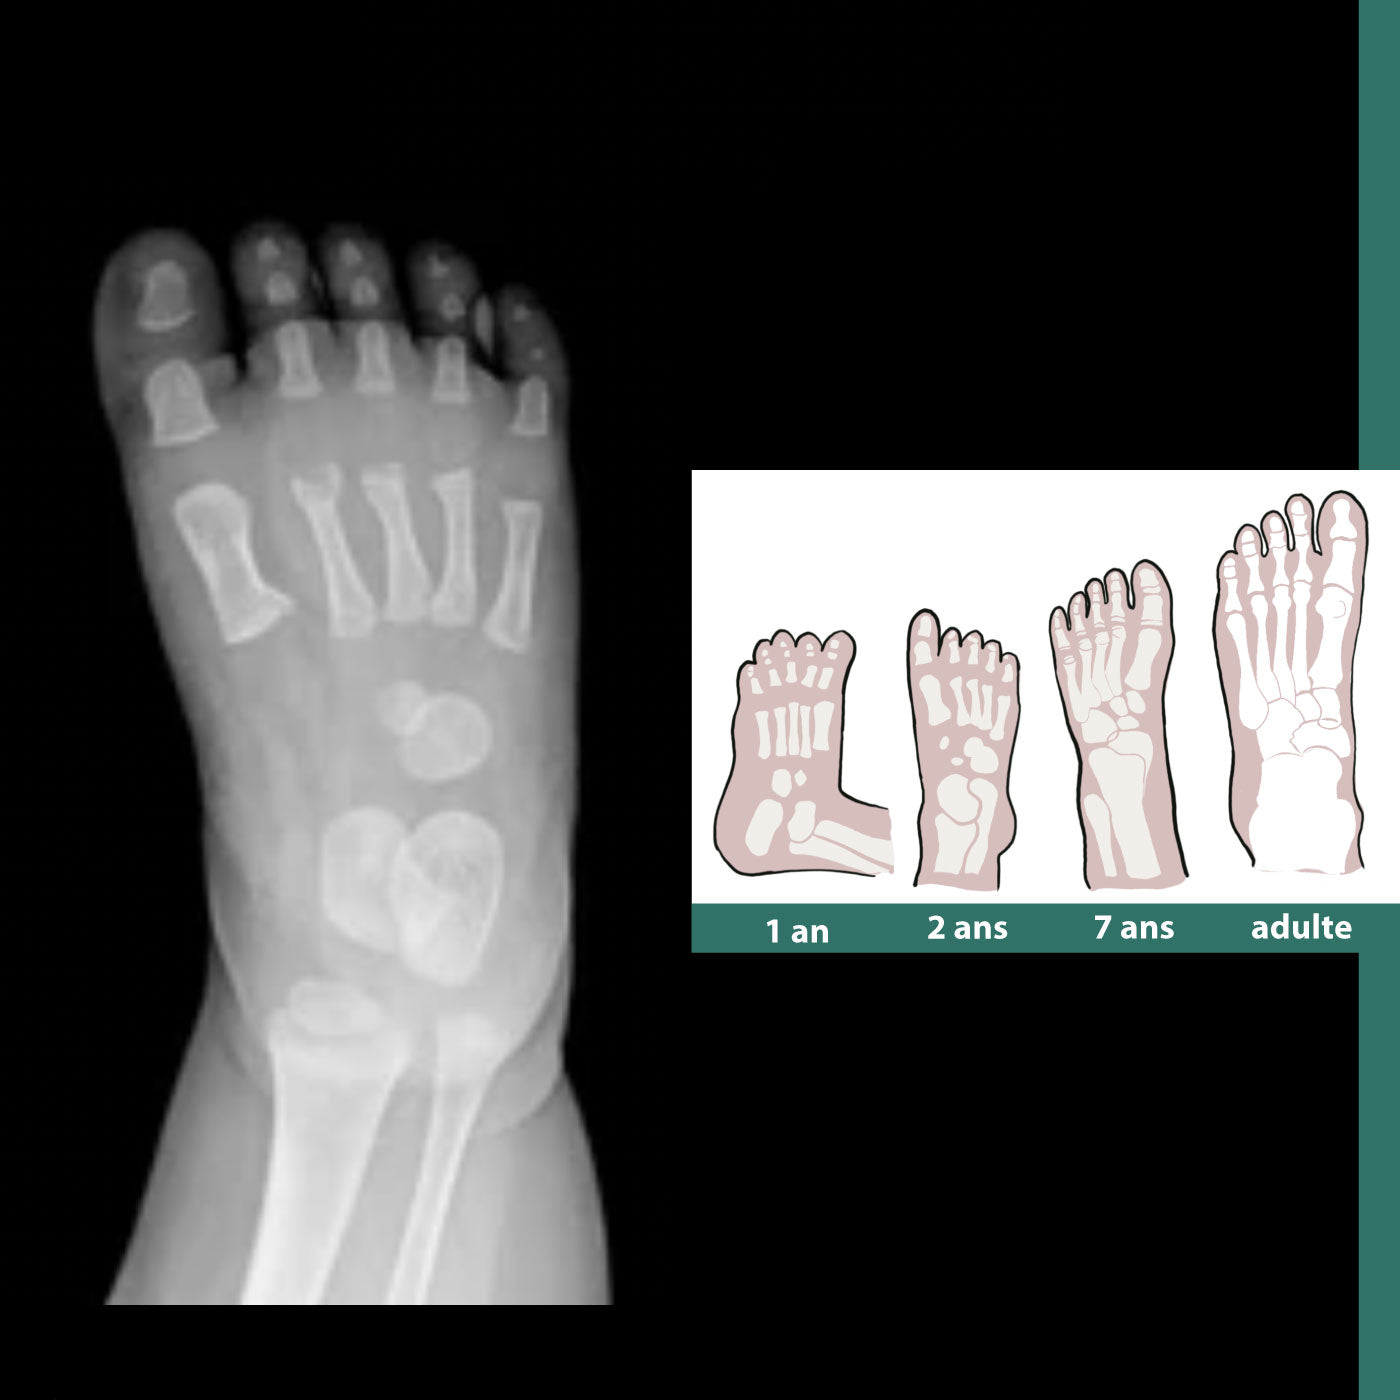

L’anatomie du pied chez le bébé est fascinante et bien différente de celle d’un adulte. Souple, malléable et encore en pleine construction, le pied du tout-petit joue un rôle essentiel dans son apprentissage de la marche. Comprendre comment il est fait, c’est aussi mieux choisir les chaussures pour ses premiers pas, celles qui l’aideront à grandir sans gêner sa motricité.

À la naissance, le pied du bébé est constitué de structures cartilagineuses qui, en grandissant, se transformeront progressivement en 26 os distincts.

Cette souplesse, associée à un coussinet plantaire épais, permet au bébé d’explorer le monde sans douleur lorsqu’il commence à se redresser. Au fil des mois, ces os vont peu à peu se solidifier pour former la véritable architecture du pied.

Chaque pied comprendra 26 os, parmi lesquels :

- le talus (ou astragale), qui relie le pied à la jambe,

- le calcanéus (ou calcanéum), qui forme le talon,

- le naviculaire, le cuboïde et trois cunéiformes,

- les cinq métatarsiens,

- et les phalanges des orteils.

Ensemble, ces éléments assurent équilibre et mobilité.